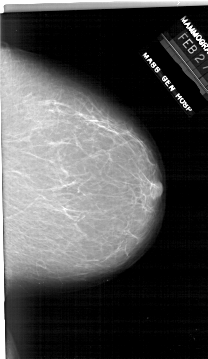

A_1916_1.LEFT_MLO

LEFT_MLO LINES 5956 PIXELS_PER_LINE 3721 BITS_PER_PIXEL 12 RESOLUTION 43.5 OVERLAY

FILE: A_1916_1.LEFT_MLO.OVERLAY

TOTAL_ABNORMALITIES 1

ABNORMALITY 1

LESION_TYPE CALCIFICATION TYPE PUNCTATE DISTRIBUTION CLUSTERED

ASSESSMENT 4

SUBTLETY 1

PATHOLOGY BENIGN

TOTAL_OUTLINES 1

BOUNDARY